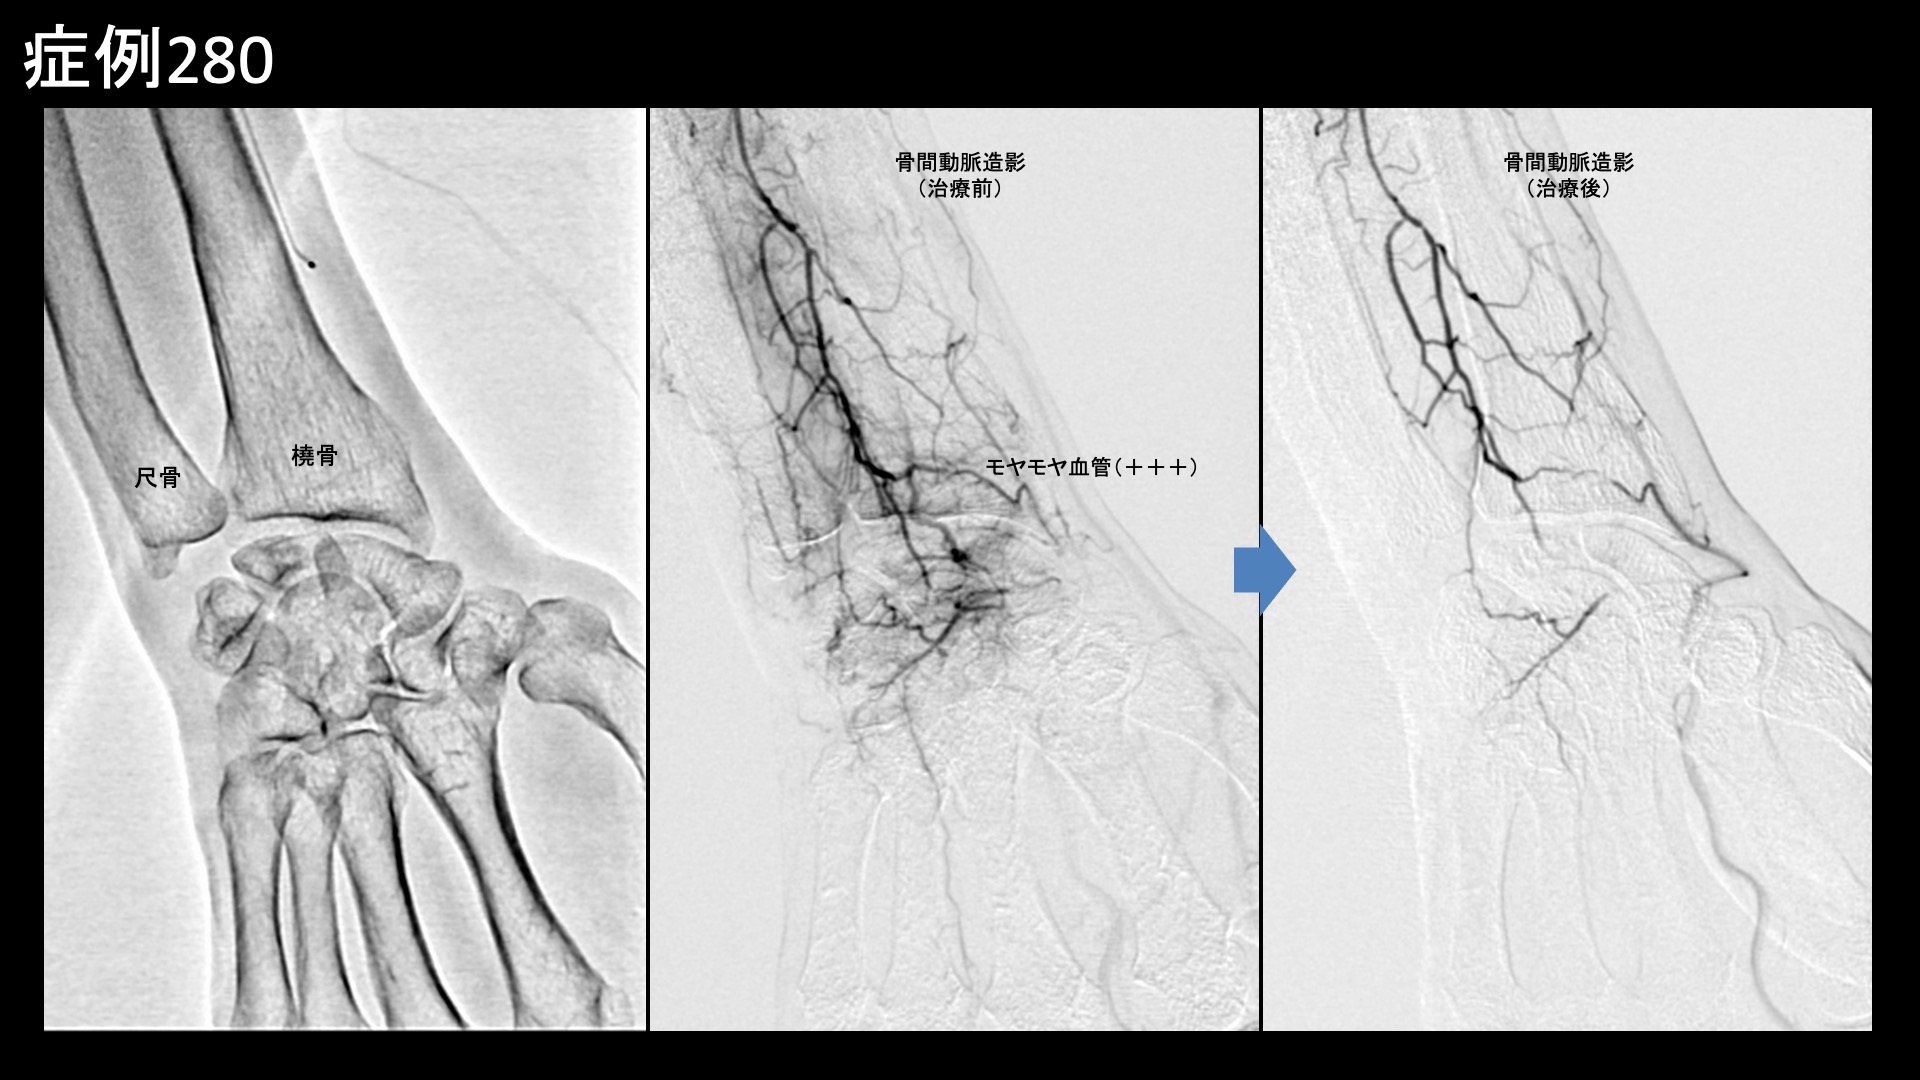

血管造影を行うと、橈骨動脈および骨間動脈にてモヤモヤ血管が濃染像として描出されました。治療後は画像上速やかに消失しました。その他複数箇所の治療を行い終了しました。

治療前画像:損傷を受ける、あるいは繰り返しのストレスにより発生した異常な新生血管

治療後画像:カテーテルを用いて塞栓物質を血管内に投与し新生血管を塞いだ状態